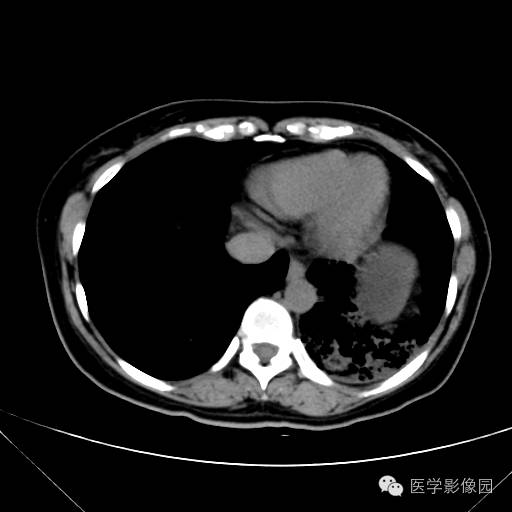

肺叶实变性支气管肺泡癌1例CT影像表现